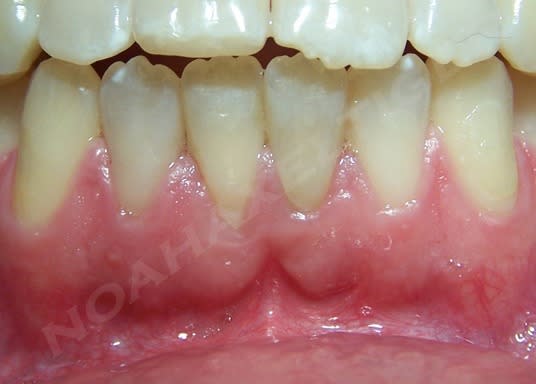

ploc écrivait:

--------------

> pr la contention le fil odf est très bien + compos

+1

Initial kardre - Eugenol

Repositionnement ka36ok - Eugenol

Rx repositionnement qraein - Eugenol

Cicatrisation  6 mois srowhm - Eugenol

mg 0207 xwjxcl - Eugenol